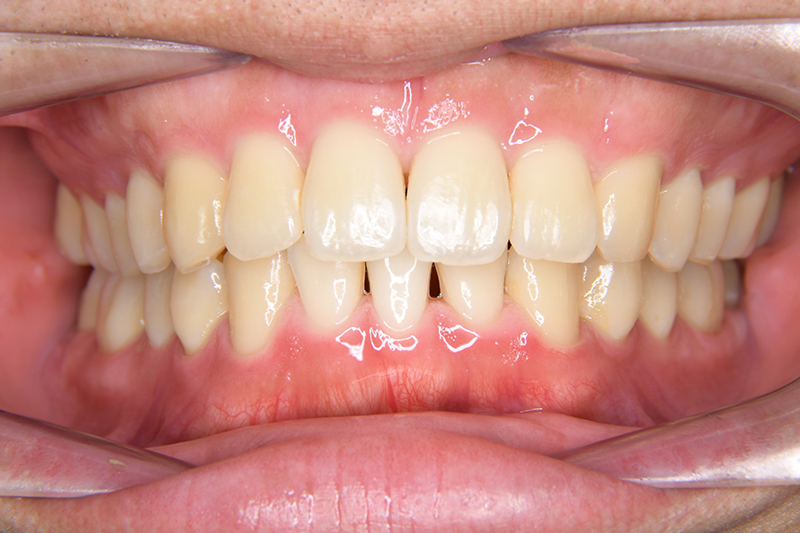

動的治療終了時

FP・IOP

批評・予后 左側臼歯uprightによって鋏状咬合、過蓋咬合の改善が得られた。下顎前歯先欠によるAnterior ratio不調和と上顎前歯部叢生の改善を目的とし、上顎前歯にIPRを行ったが、治療後において左上2付近のover jetが大きく、上顎犬 歯間幅径の拡大(1.5mm)も生じているため、後戻りの懸念が残る。口元や歯列の安定性を考慮し、小臼歯抜歯も検討したがハイアングルであり下顎3-incisalのため、治療が困難となる事を危惧して非抜歯にて治療を行った。